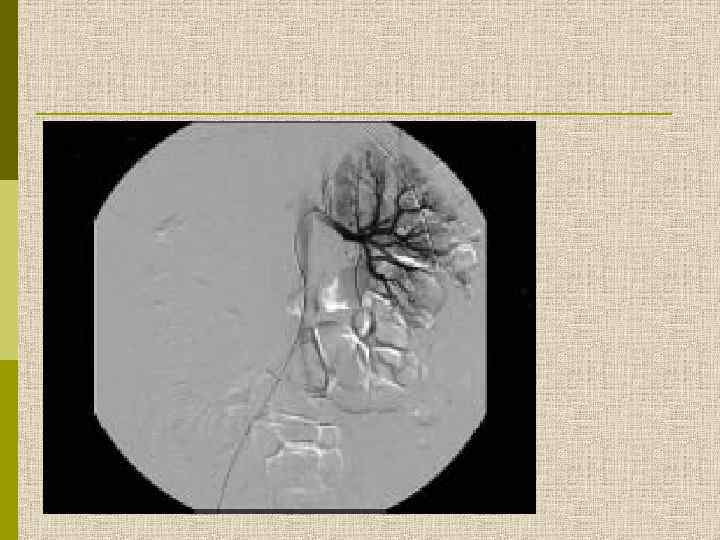

Артериограмма почки при узелковом полиартериите. Микроаневризмы мелких артерий, окклюзия больших артерий. Rose BD, 1987

Почечные аневризмы при узелковом полиартериите, ассоциированном с гепатитом В Chauveau D. , Christophe J-L. N Engl J Med 1995; 332: 1070